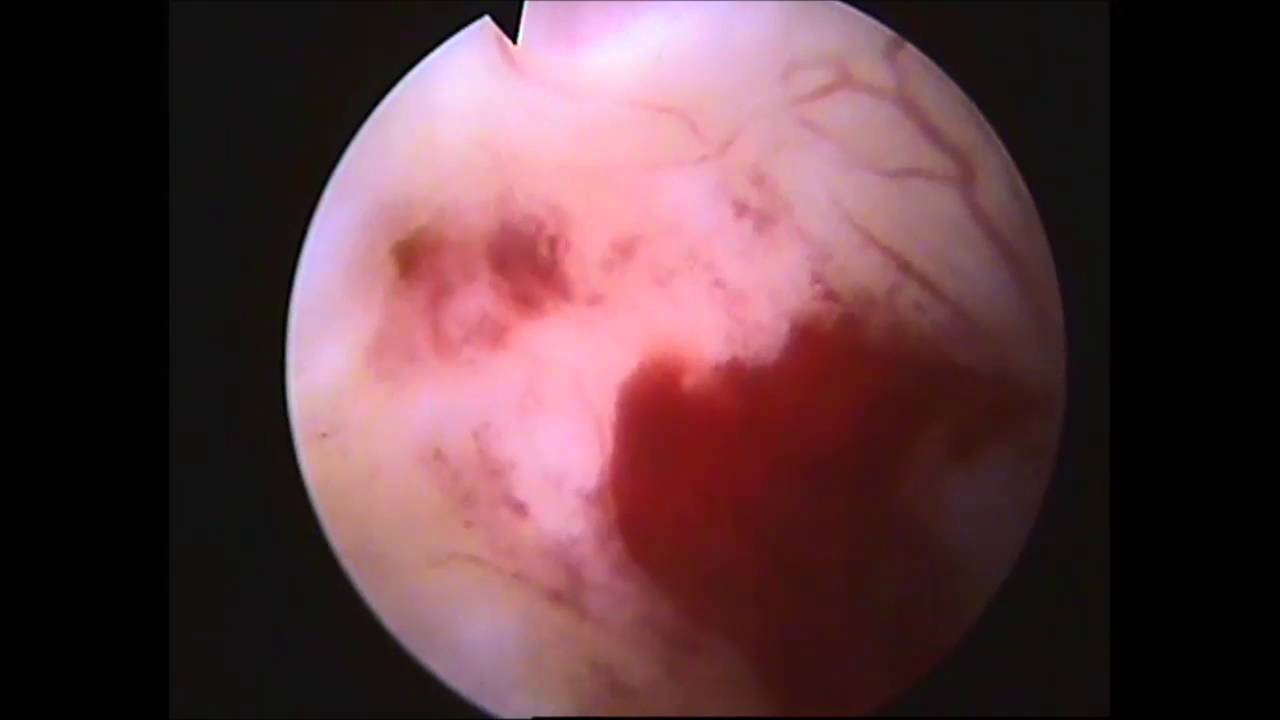

Кроме УЗИ, врач может рекомендовать проведение гистероскопии. Этот метод исследования подходит только для женщин, не находящихся в положении, так как он может представлять опасность для плода. Например, гистероскопия необходима в случаях, когда женщине требуется пластика рубца на матке после кесарева сечения.